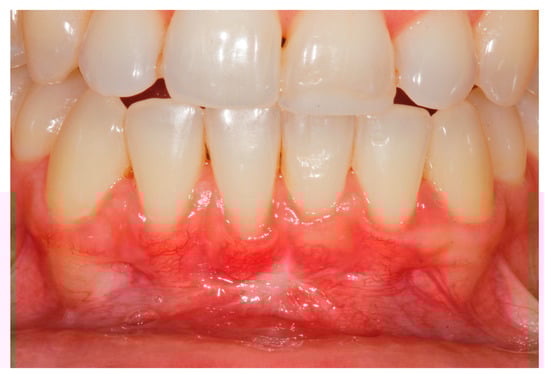

2. Case Study